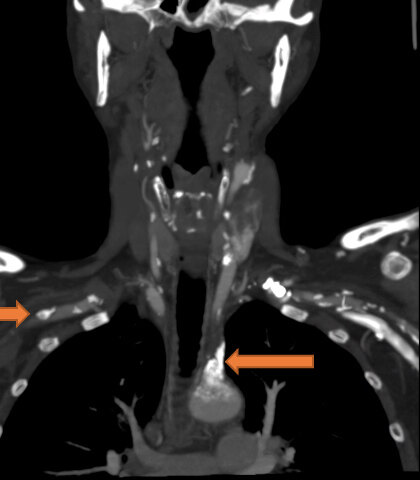

?家住綏化市的李大爺在一個月前發(fā)現(xiàn)自己左上肢血壓較右上肢低,左上肢脈搏觸摸不清,左上肢無力,并伴有頭暈、頭疼的癥狀。近一周癥狀逐漸加重,并出現(xiàn)左側(cè)手指涼麻及左手活動受限等癥狀。為求明確病因,家屬帶李大爺來到了哈醫(yī)大四院找到黃任平教授。???????黃任平主任查體后發(fā)現(xiàn)患者左上肢皮溫低于右上肢,左上肢橈動脈搏動十分微弱,左上肢血壓比右上肢低了一大截。進一步行血管彩超回報患者左側(cè)鎖骨下動脈竊血,考慮鎖骨下動脈起始段完全閉塞,CTA證實了左鎖骨下動脈起始段完全閉塞。黃任平主任考慮患者已經(jīng)患病一月余,且有癥狀逐漸加重趨勢,如不及時開通閉塞血管,可能導(dǎo)致頭暈癥狀加重及大面積腦梗風(fēng)險。經(jīng)過縝密的術(shù)前準備后,黃任平主任帶領(lǐng)血管外科團隊為李大爺實施手術(shù)治療。?術(shù)中造影可見鎖骨下動脈閉塞,左側(cè)鎖骨下動脈盜血,椎動脈反流。黃任平主任首先用導(dǎo)絲穿過閉塞的血管,然后應(yīng)用球囊對病變血管進行球囊擴張,最后于閉塞處植入一枚血管支架,手術(shù)全程只用20分鐘,患者即刻左胳膊摸脈搏動有力,左上肢乏力減輕,左手涼麻癥狀消失,左手功能逐漸恢復(fù)正常。?黃任平主任介紹,患者左上肢血壓較右側(cè)低及左側(cè)上肢肢體涼麻疼痛等癥狀都是由于鎖骨下動脈閉塞缺血導(dǎo)致,而患者頭暈癥狀是由于盜血綜合征導(dǎo)致。鎖骨下動脈盜血綜合征是指無名動脈或鎖骨下動脈分出椎動脈之前的近心端發(fā)生部分性或完全性閉塞時,由于虹吸作用,引起患側(cè)椎動脈血液逆流,反向供應(yīng)缺血的患側(cè)上肢,結(jié)果導(dǎo)致椎-基底動脈缺血性發(fā)作和患側(cè)上肢的缺血癥狀的一組癥候群。主要臨床表現(xiàn)為眩暈、頭痛、復(fù)視、患側(cè)上肢無力、易疲勞等癥狀。體征方面表現(xiàn)為,患側(cè)上肢橈動脈、肱動脈搏動減弱或消失。患側(cè)上肢血壓下降,一般多數(shù)下降20-50mmHg,長時間供血不足可導(dǎo)致患肢肌肉萎縮,手指、手掌皮溫低,嚴重者可導(dǎo)致腦梗。所以當(dāng)廣大患者存在上述癥狀時不要忽視鎖骨下動脈閉塞的可能,應(yīng)及時前往血管外科就診,以免延誤最佳治療時機。黃任平醫(yī)學(xué)博士、博士后,碩士生導(dǎo)師哈爾濱醫(yī)科大學(xué)附屬第四醫(yī)院血管外科主任專業(yè)方向:擅長血管外科的常見病多發(fā)病的診治,從事微創(chuàng)血管病治療與創(chuàng)面治療10余年,治愈各種靜脈曲張、糖尿病足、下肢靜脈血栓、脈管炎、動脈硬化閉塞癥、胸腹主動脈瘤、動脈栓塞、肺栓塞、鎖骨下動脈閉塞、腎動脈狹窄、嬰幼兒血管瘤、血管畸形等20000余例。血管外科門診出診醫(yī)生一覽表出診醫(yī)生出診時間黃任平周一、周二上午8:00-11:30李佳樂周一、周二下午13:00-16:30謝春楊周三、周四上午8:00-11:30馬文超周五上午8:00-11:30出診地點:哈爾濱醫(yī)科大學(xué)附屬第四醫(yī)院門診三樓C區(qū)外科3診室咨詢電話:0451-82576869